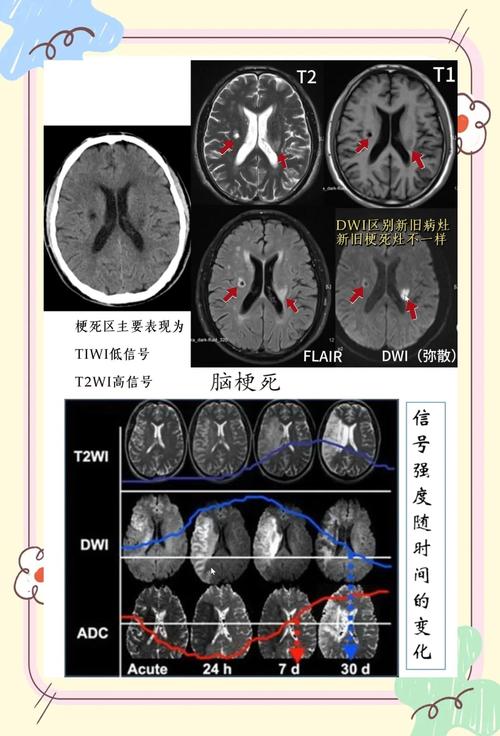

- CT不是万能的! 对于超早期的脑梗,MRI(磁共振)特别是DWI序列(弥散加权成像)比CT敏感得多,能更早地发现病灶。